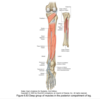

Muscles of posterior compartment of leg

Superficial: gastrocnemius, plantaris, soleus

Deep: popliteus, flexor hallucis longus, flexor digitorum longus, tibilais posterior

Origin and insertion of gastrocnemius

Medial and lateral condyle to calcaneus

Origin and insertion of plantaris

Lateral supracondylar line of femur to calcaneus

Origin and insertion of soleus

Soleal line/medial tibia to calcaneus

Innervation to posterior compartment of leg

tibial nerve

Origin and insertion of popliteus

Lateral femoral condyle to posterior tibia

Origin and insertion of flexor hallucic longus

posterior fibula to distal phalanx f big toe

Origin and insertion of flexor digitorum longus

Tibia to distal phalanges of lateral 4 toes

Origin and insertion of tibialis posterior

Interosseus membrane to tuberosity of navicular bone